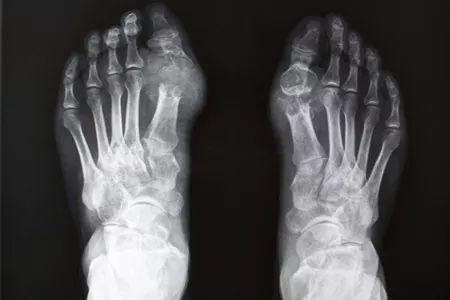

抓住时机及时治疗

成都风湿医院痛风科陈建春提醒:痛风不是简单的关节痛,它是一种全身性的疾病,因此必须接受专业、正规的治疗。本期节目中,该患者若是能一开始便前往正规医院就诊,听从专业医生的建议,也不至于盲目放任病情发展。陈建春主任指出:痛风病情发展到后期,会造成骨质的破坏以及其他器官的损坏等,治疗难度也不断加大,因此要尽早抓住关键治疗时期,避免走进痛风治疗的误区,贻误康复。